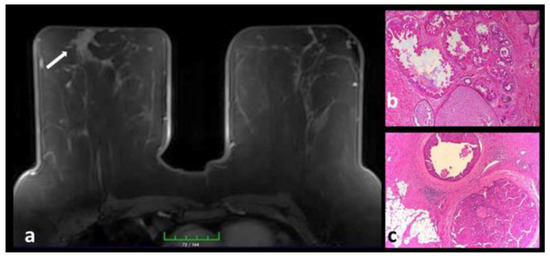

Juvenile Papillomatosis